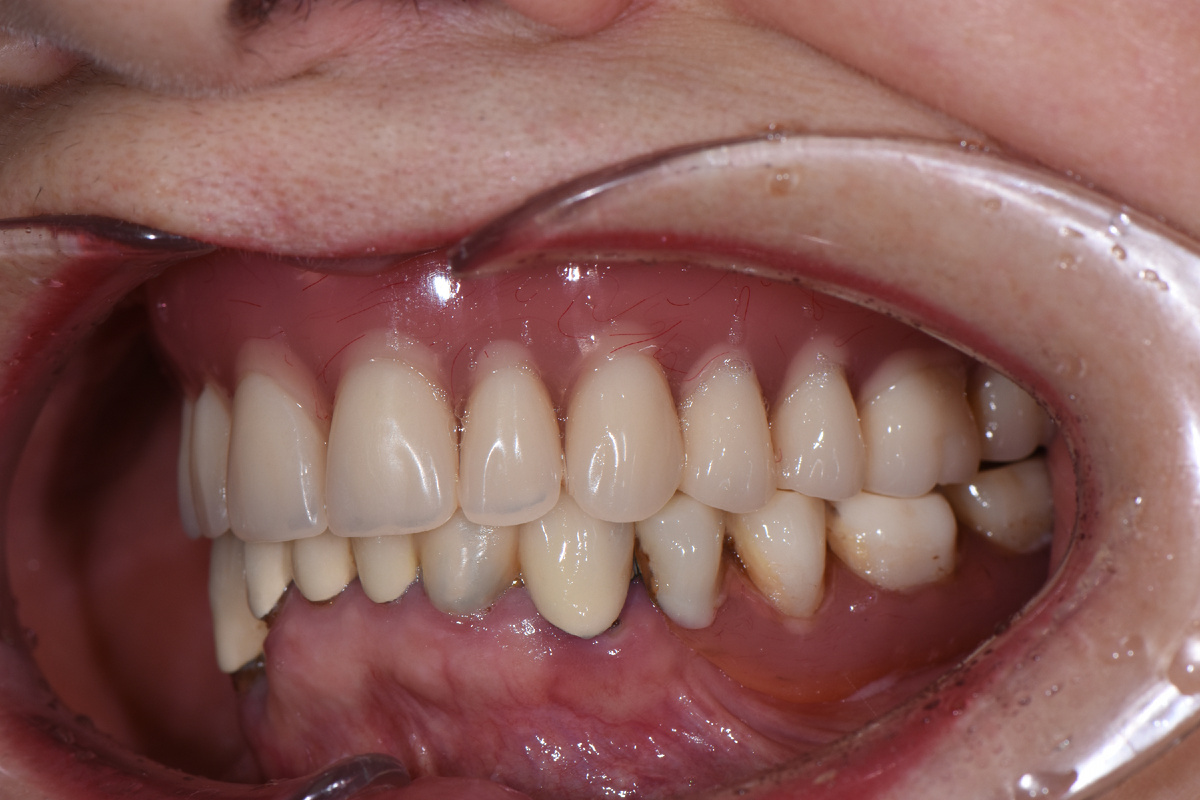

Результат ❗️всего через месяц❗️ после мягкотканной операции на фото ниже 👇

Честно говоря, до сих пор регенераторные возможности организма кажутся невероятными 💪

Обратите внимание на то, каким массивным сформировался слой мягких тканей на внешней стороне челюсти. В том месте, где мы смещали лоскут.

А также виден небольшой "провал" десны по всей длине альвеолярного гребня, где мы укрывали надкостницу мембраной. В течение 3-4 месяцев объем десны восстановится и в этом участке.